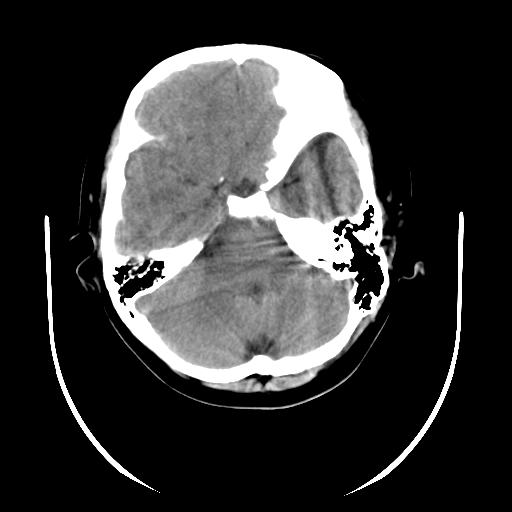

女,6岁,头痛、呕吐一天。

颅脑ct平扫未见明显异常。

头颅ct平扫未见明确异常,随诊复查。